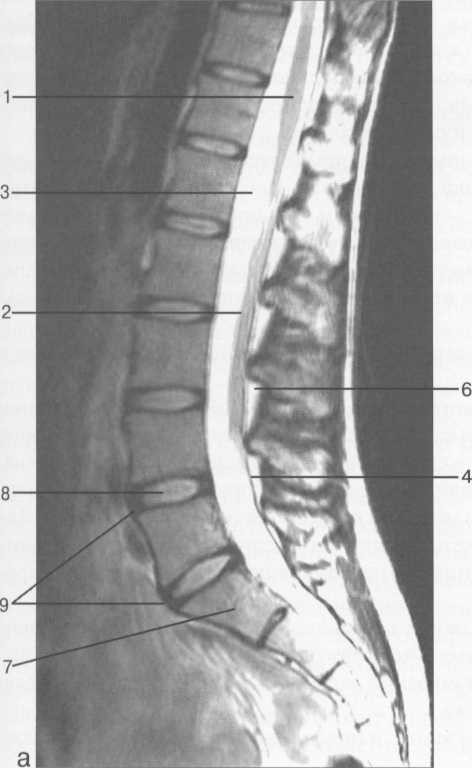

МРТ исследования дают широкую возможность исследовать  все структуры спинного мозга в разных плоскостях. ( рис. 37-41 )

Рис. 37. Срединные сагиттальные МРТ пояснично-крестцового отдела позвоночника.

а-Т2-ВИ;б-Т1-ВИ.

1 -- конус спинного мозга; 2 -- конский хвост спинного мозга; 3 -- субарахноидальное пространство; 4 -- дуральный мешок; 5 -- терминальная нить; 6 -- эпидуральное пространство; 7 -- тело Sp 8 -- пуль­позное ядро межпозвонкового диска; 9 -- фиброзное кольцо межпозвонкового диска; 10 -- каналы бази-вертебральных вен; 11 -- остистый отросток LIV.